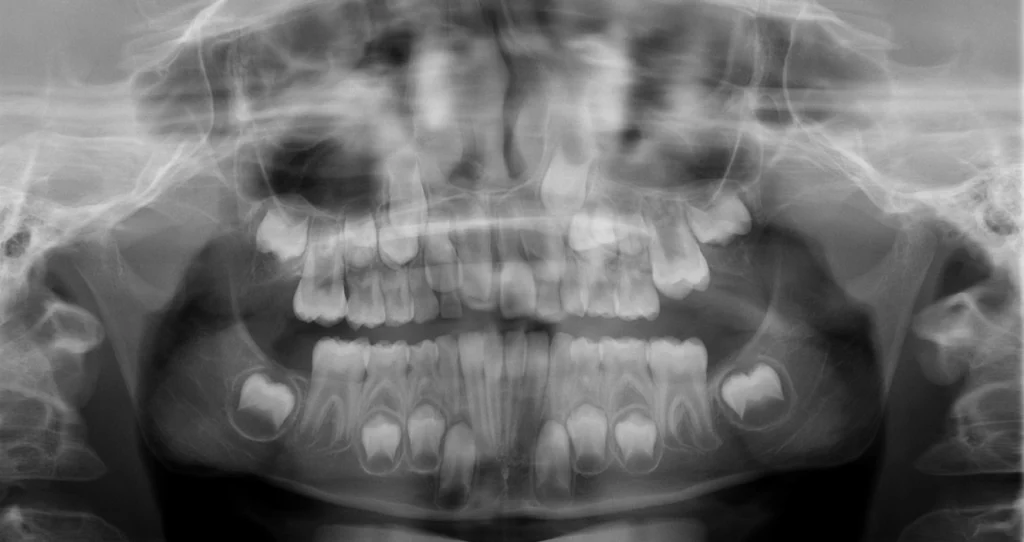

- OPG (Panoramatická snímka): Toto vyšetrenie robíme štandardne v období výmeny chrupu, teda medzi 5. až 8. rokom života, keď sa prerezávajú prvé trvalé stoličky („šestky“). Snímka nám ukáže postavenie všetkých zubov, vrátane tých, ktoré ešte nie sú prerezané.